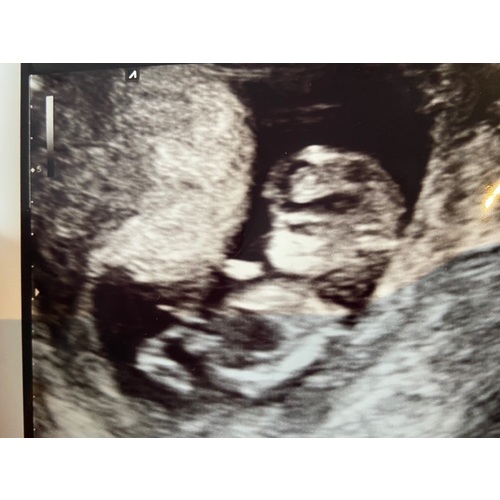

Ze gaf aan dat ze aan een cyste of ruimte met vocht dacht maar ze kon het echt niet zeggen omdat ze het nog nooit gezien had. Leek vanaf het middenrif en dan omlaag te zitten bijna ruimte vullend. Echt een zwarte plek.

Verder groeide het kindje goed en zag alles er voor de rest voor nu goed uit. Maar het zwarte vlekje was zo groot als de hele buik ongeveer + het hartje zat in de verdrukking dus dat baarde haar ook zorgen. We moesten van het ergste uit gaan! Je wereld staat in een keer op zijn kop. Maar je wil antwoorden (en het liefst horen dat het goed komt) maar die krijgen we voorlopig nog even niet.

Even een update; gister hadden we onze afpsraak in het radboud. Een hele uitgebreide echo van meer dan een uur volgende. Wat we allebei meteen zagen was dat die gekke zwarte plek minder was geworden. Veeeeel minder! Ons kindje is van top tot teen nagekeken. Ons kindje zag er voor nu goed uit, jeetje!! Die gekke plek, ze denken aan een cyste, was van 1,5cm naar 3mm gegaan. En was voor nu geen gevaar meer. Wij waren er op voorbereid dat het hartje niet meer klopte. Wat een fantastisch nieuws.. maar zo spannend en angstig hoe het verloop gaat zijn. 6 november weer een uitgebreide echo, hopelijk gaat alles goed en ontwikkeld de kleine zich goed. 🙌🏻